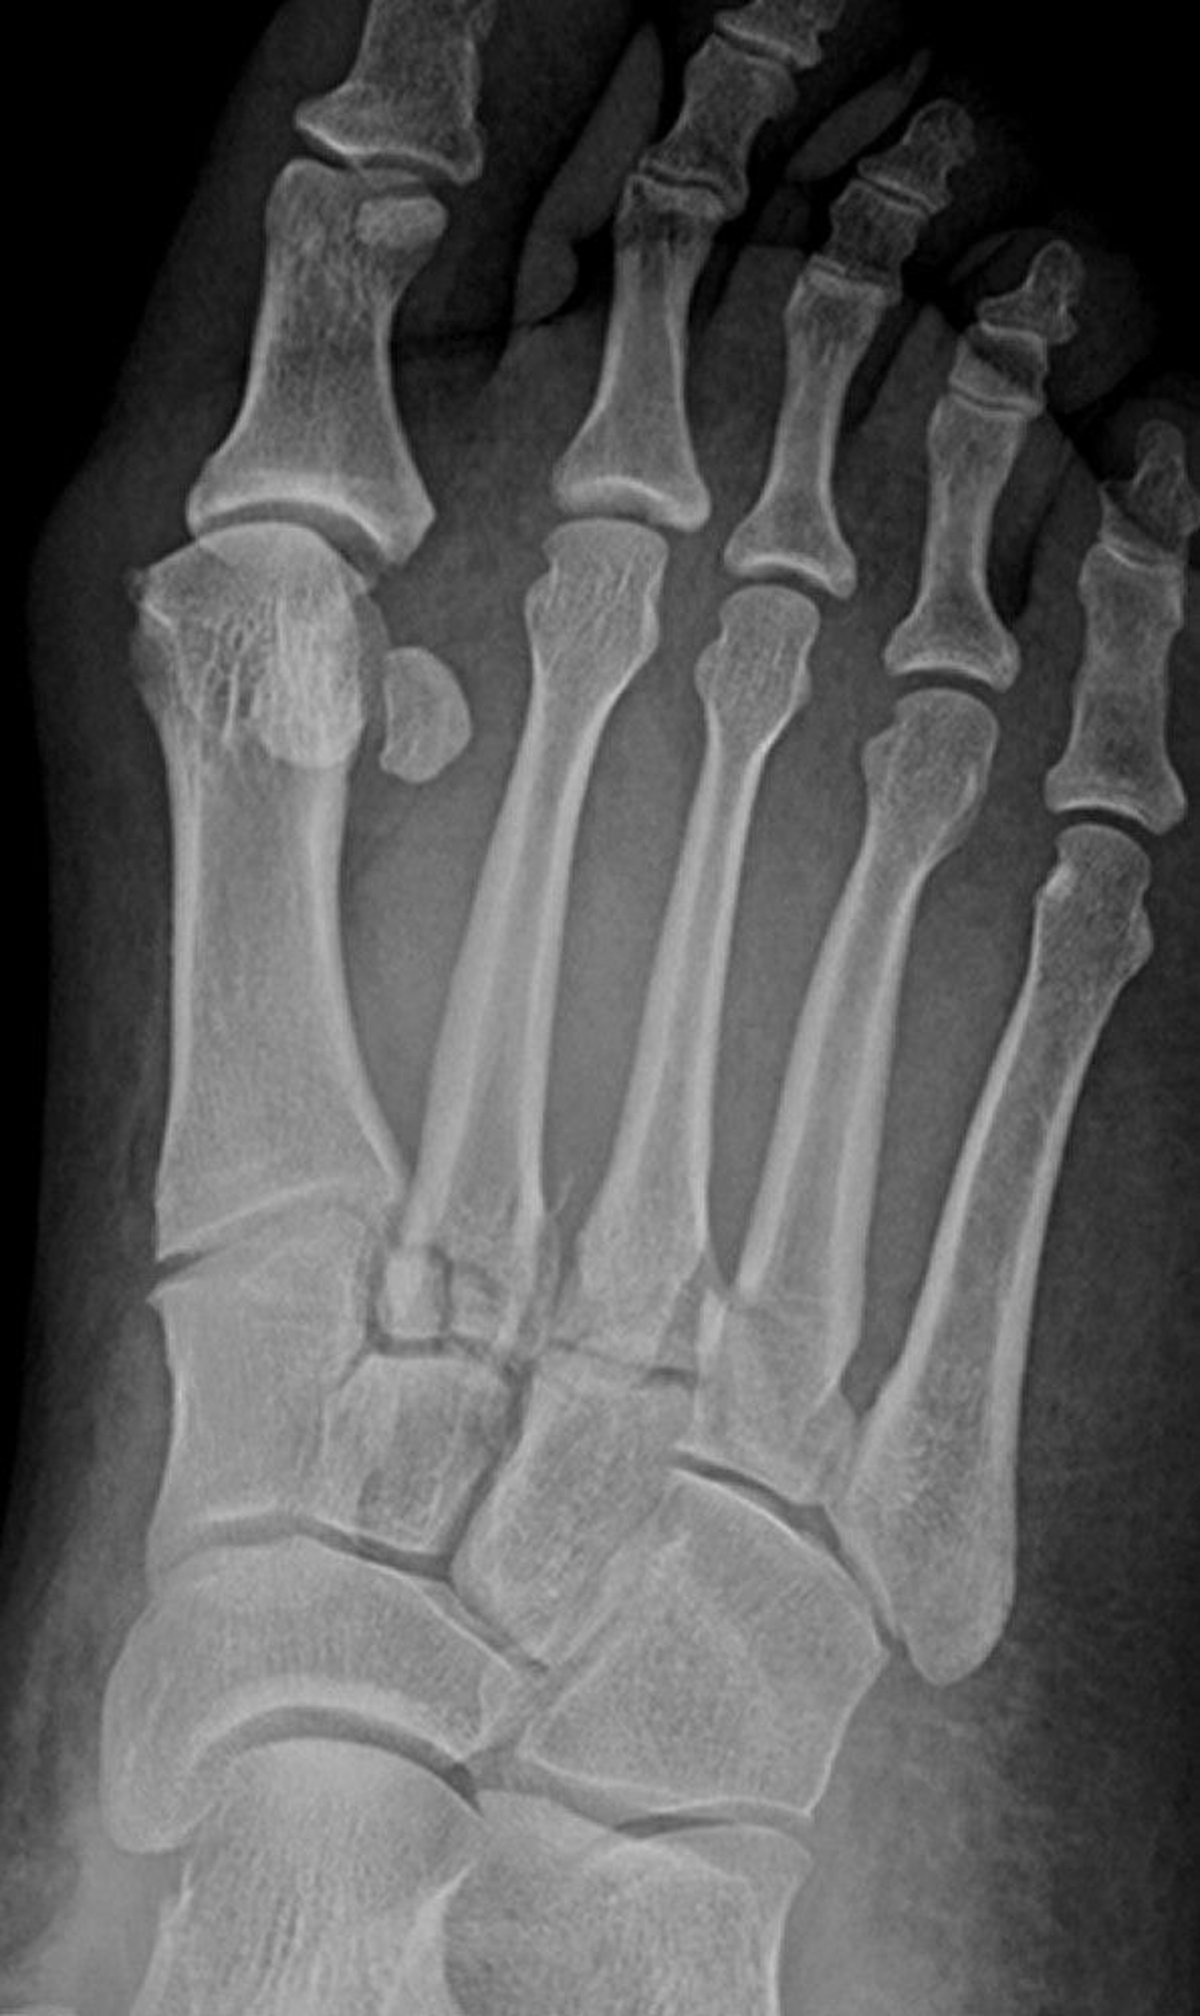

Lisfranc Fractures

This radiograph shows fractures at the base of the 2nd, 3rd, and 4th metatarsals. The tarsometatarsal joints are also disrupted.

Image courtesy of Danielle Campagne, MD.